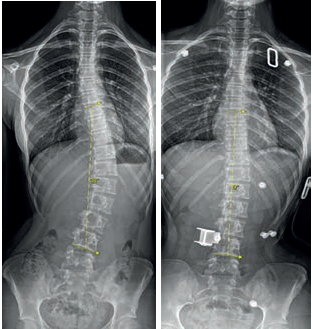

Obr. 1 Thorakolumbální skolióza Lenke typ 5 (Th11 – 23 sin. – L3), CSVL C – křivka tedy vykazuje abnormalitu ve frontální rovnováze. KO = koncový obratel; VO = vrcholový obratel. Horizontální linie procházející stříškami pánevních acetabul vylučuje asymetrii výšek kyčelních kloubů. Zdroj: Ortopedická klinika FZS UJEP a MN UL.Jedná se o jeden z aktuálně používaných klasifikačních systémů, díky němuž lze popsat až 42 typů křivek. Lenke rozlišuje šest základních typů deformit, které jsou děleny dle lokalizace a jednotlivých typů patologických křivek páteře. V rámci tohoto systému může být dále hodnocen tzv. lumbar modifier A–C dle průběhu tzv. centrální sakrální vertikální linie (CSVL), případně tzv. thoracic sagittal modifier, kdy je na sagitálních snímcích determinována eventuální hyper‑/hypokyfóza.11 Základní hodnocení skoliotické křivky popisuje obrázek 1.

• Cobbův úhel – hlavní parametr skoliotické křivky. Při jeho konstrukci nejprve určíme koncové obratle, které ohraničují skoliotickou křivku kraniálně a kaudálně. Následně zakreslíme tečny jejich odlehlých krycích lišt (tedy horní lišta u kraniálního obratle a dolní lišta u kaudálního obratle), z těchto tečen poté sestrojíme kolmice. Doplňkový úhel v oblasti jejich průsečíku je úhlem Cobbovým. Sestrojení Cobbova úhlu je popsáno na obrázku 1.